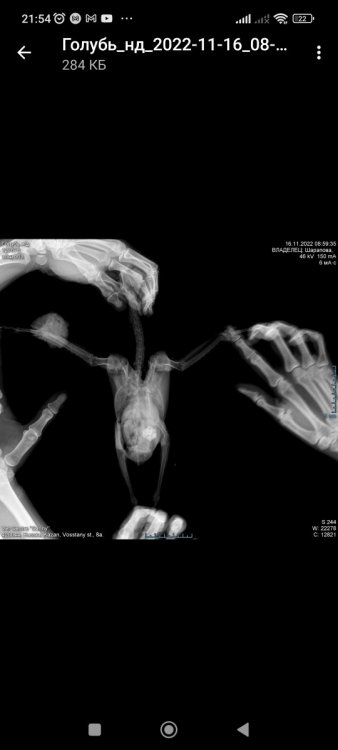

Zosia Опубликовано 21 ноября, 2022 #7 Опубликовано 21 ноября, 2022 нарост (по виду старый абсцесс, зафибриненный)- омывать смесью №2, и внутри тоже. Пероо у основания все состричь, контролировать "ножку". На рентгене все кости перавого крыла сохранены, правда немного рыхло выглядят ,но возможно такой ракурс, крыло чуть повернуто. 3